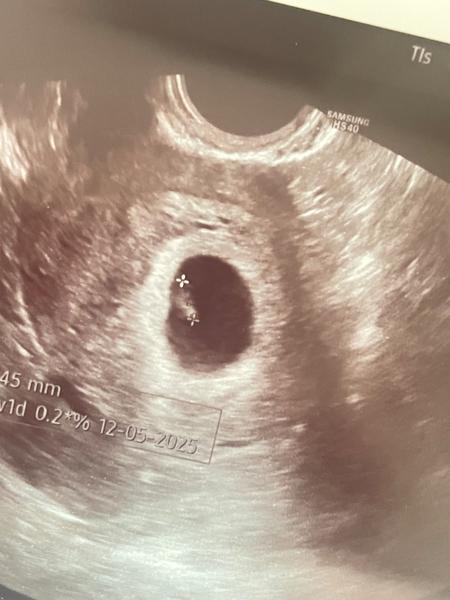

@vlasta1981 holky❤️ tak po týdnu update. Jsem 6+1 dle utz. A embryjko i srdicko byly videt❤️mam radost.

Blahozelam 😍😍

@katezina11 dekuji❤️

Moc gratuluji 🍀

Gratuluju 🍀🍀

@vlasta1981 dekuji holky 🙂